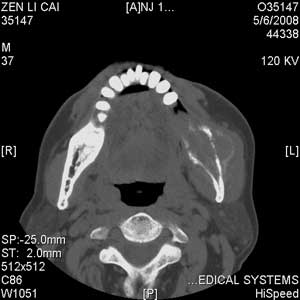

以下是引用jiangjing在2008-5-28 15:56:00的发言:[br]下颌骨左侧部骨质破坏,轻度膨胀,瘤骨形成,软组织肿胀考虑 恶性骨肿瘤-----肉瘤类